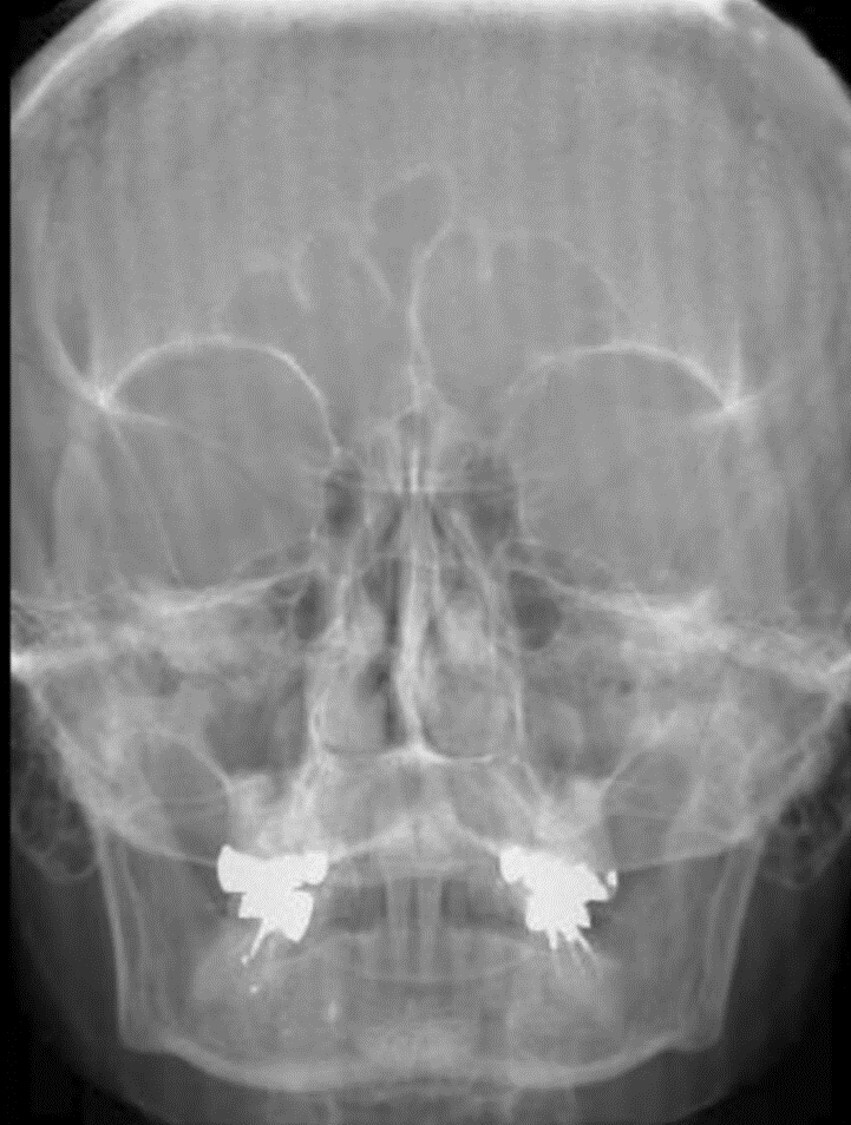

What is the cause of the artifact seen in the

attached image?

A

Upside-down focused grid resulting in grid cut-off